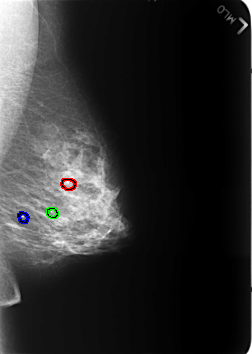

B_3235_1.LEFT_MLO

FILE: B_3235_1.LEFT_MLO.OVERLAY

TOTAL_ABNORMALITIES 3

ABNORMALITY 1

LESION_TYPE CALCIFICATION TYPE ROUND_AND_REGULAR-LUCENT_CENTER DISTRIBUTION N/A

ASSESSMENT 2

SUBTLETY 5

PATHOLOGY BENIGN_WITHOUT_CALLBACK

ABNORMALITY 2

ABNORMALITY 3